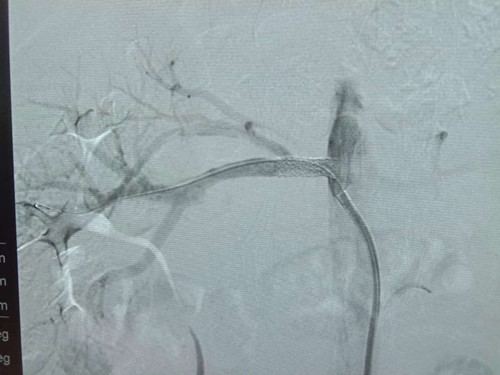

近日,我院内分泌科收治了一名年轻患者,28岁,男性,血糖升高6年,头晕伴左手麻木3天。经过完善的相关检查,诊断为:2型糖尿病、糖尿病酮症、糖尿病肾病、急性脑梗死、高血压3级很高危。在给予有效降糖、降压、营养脑细胞等治疗下,内分泌科联合介入中心对患者进行全脑血管造影及肾动脉造影,造影显示右侧肾动脉重度狭窄(狭窄率80%),左侧椎动脉重度狭窄(狭窄率80%),经过进一步仔细检查,分析病情,最终考虑患者多年的高血压病为肾动脉狭窄所致,决定对患者进行肾动脉支架置入术及球囊扩张术,手术于06-14上午9点开始,经过1.5小时治疗,支架顺利植入右侧肾动脉,左侧肾动脉成功进行球囊扩张,双侧肾动脉血流明显改善,术后患者血压下降并维持正常。患者年龄较小,但是多年的糖尿病及高血压病导致大血管病变较重,经过此次介入精准治疗,使患者的高血压病得以缓解,明显降低了靶器官损害的风险。